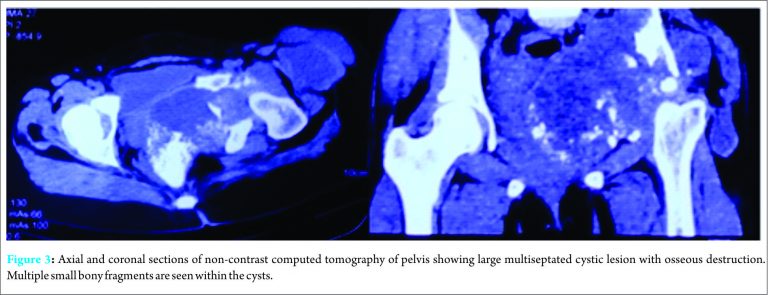

This prompted an ultrasound of the hepatobiliary system which revealed a well-circumscribed multilobulated lesion in segment V of the right lobe of the liver with peripheral daughter cysts. There was an associated large exophytic component extending medially beyond the hepatic capsule, suggestive of hydatid cyst. Henceforth, abdominal computed tomography (CT) scan with contrast (Fig. 2) was done revealing 10.2 cm × 5.6 cm exophytic multiseptated thick-walled cystic lesion arising from the right lobe of the liver. There was an associated smaller (3.3 cm × 2.3 cm) multiseptated cystic lesion with evidence of rim calcification. CT scan of the pelvis (Fig. 3) revealed a large multiseptated cystic lesion with the osseous destruction of the left iliac bone, acetabulum, and proximal femur. It showed complete destruction of the acetabulum with evidence of protrusio acetabuli. The cystic component of the lesion involved muscles around the hip joint and left hemipelvis. This extended into the ischiorectal fossa, gluteal region, and iliopsoas, with a cold abscess in pelvis tracking along the anterolateral aspect of the thigh. Multiple small bony fragments were seen in the cystic lesion.